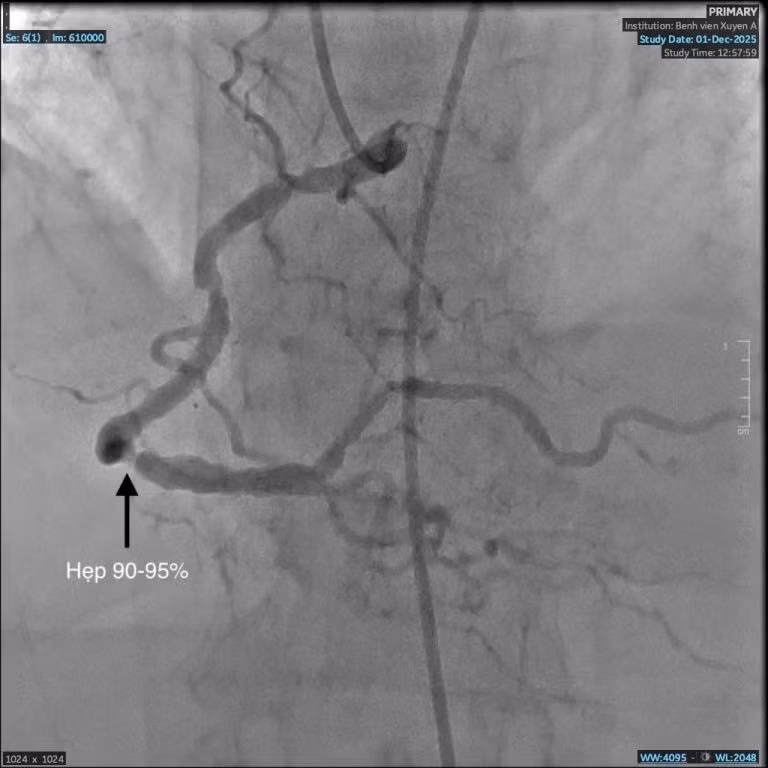

Mạch máu hẹp trước can thiệp - Ảnh BVCC

Mạch máu trước can thiệp hẹp đến 95% - Ảnh BVCC

Kết quả chụp động mạch vành phát hiện bà C. bị hẹp nặng ba nhánh mạch vành, rơi vào nguy kịch nhồi máu cơ tim. Đây là nguyên nhân chính khiến bà khó thở, đau nặng ngực.